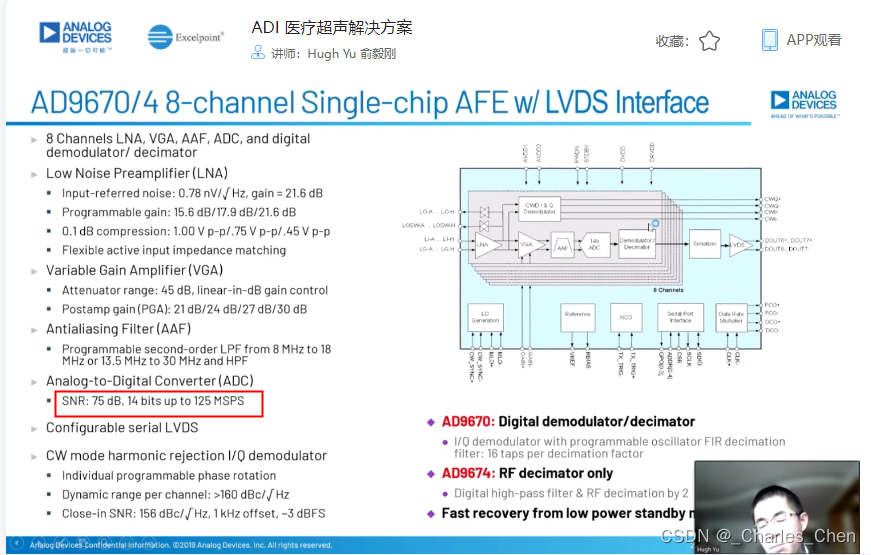

成像通道接收机

超声成像通道的接收机用于检测二维(2D)信号以及彩超流体成像所需的脉冲多普勒(PWD)信号和频谱PWD。接收机包括Tx/Rx开关、低噪声放大器(LNA)、可变增益放大器(VGA)、抗混叠滤波器(AAF)和模/数转换器(ADC)。

低噪声放大器(LNA)

可变增益放大器(VGA)

抗混叠滤波器(AAF)和ADC

典型应用中采用12位ADC,采样率通常在40Msps至60Msps之间。ADC提供必要的瞬态动态响应范围,同时具有适当的成本和功耗。在设计得当的接收器中,ADC会限制接收通道的瞬态SNR。如上所述,性能差的VGA会限制整个接收通道的SNR指标。